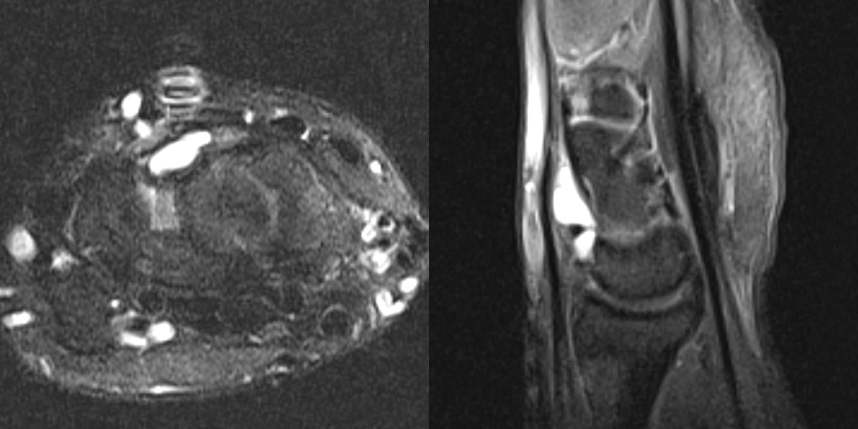

손목 앞쪽의 결절종이 있었지만, 뿌리는 손등쪽하고 연결된 까다로운 경우의 MRI 입니다.

만약 MRI 를 찍지 않았다면 손목 앞쪽에 보이는 결절종만 제거하여 재발 가능성이 높을 수 있는 경우입니다.

이 환자의 경우 앞, 뒤에 절개를 넣어 뿌리까지 제거해주어 재발 없이 유지되었습니다.